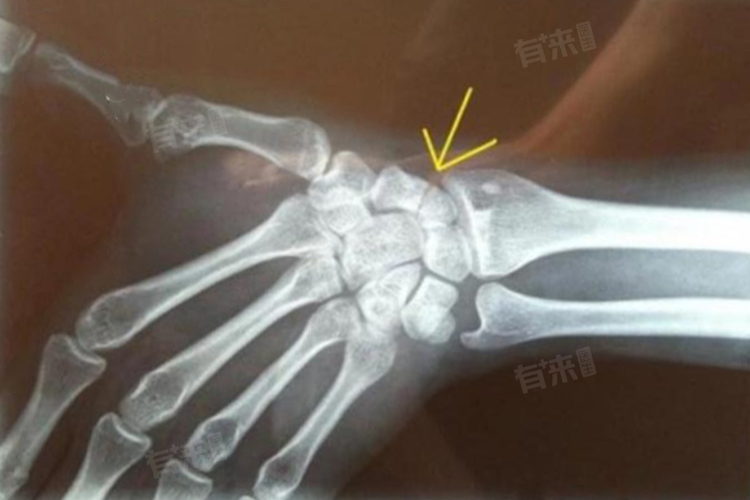

3、严重程度:如果是简单裂缝骨折或轻度的撕脱骨折,没有出现明显移位,一般6-8周后骨折可以基本愈合,经过适当的功能锻炼,3-4个月可基本恢复正常功能。若是骨折有明显的移位或者合并有关节脱位等,恢复时间会明显延长,大概为6-12个月。